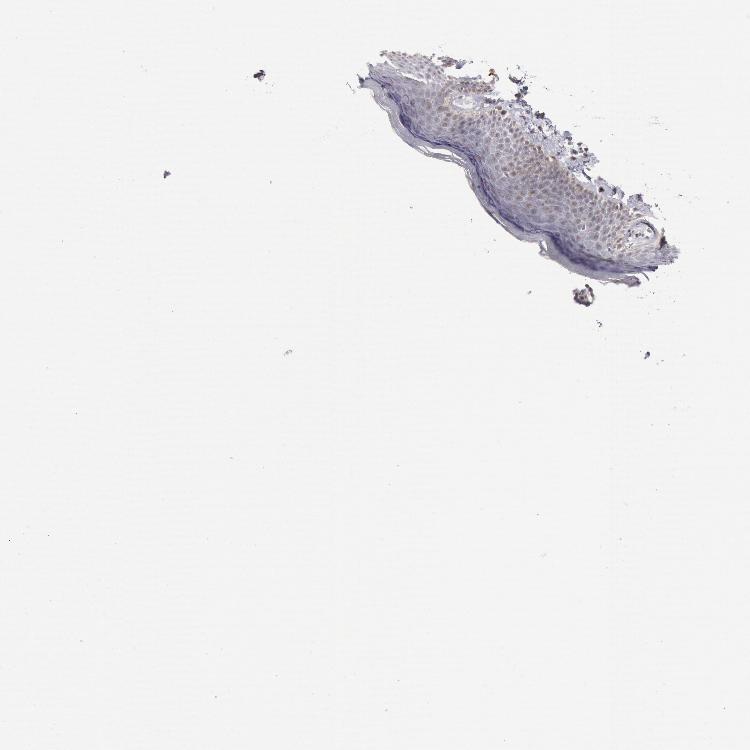

SKIN 1 - Antibody stainingi

Antibody staining in the annotated cell types in the current human tissue is reported as not detected, low, medium, or high, based on conventional immunohistochemistry profiling in selected tissues. This score is based on the combination of the staining intensity and fraction of stained cells.

Each image is clickable and will lead to virtual microscopy that enables deeper exploration of all samples and also displays staining intensity scores, fraction scores and subcellular localization as well as patient and tissue information for each sample.

Antibody HPA001168

Langerhans Not detected

Fibroblasts Not detected

Keratinocytes Not detected

Melanocytes Not detected

SKIN 2 - Antibody stainingi

Epidermal cells Not detected